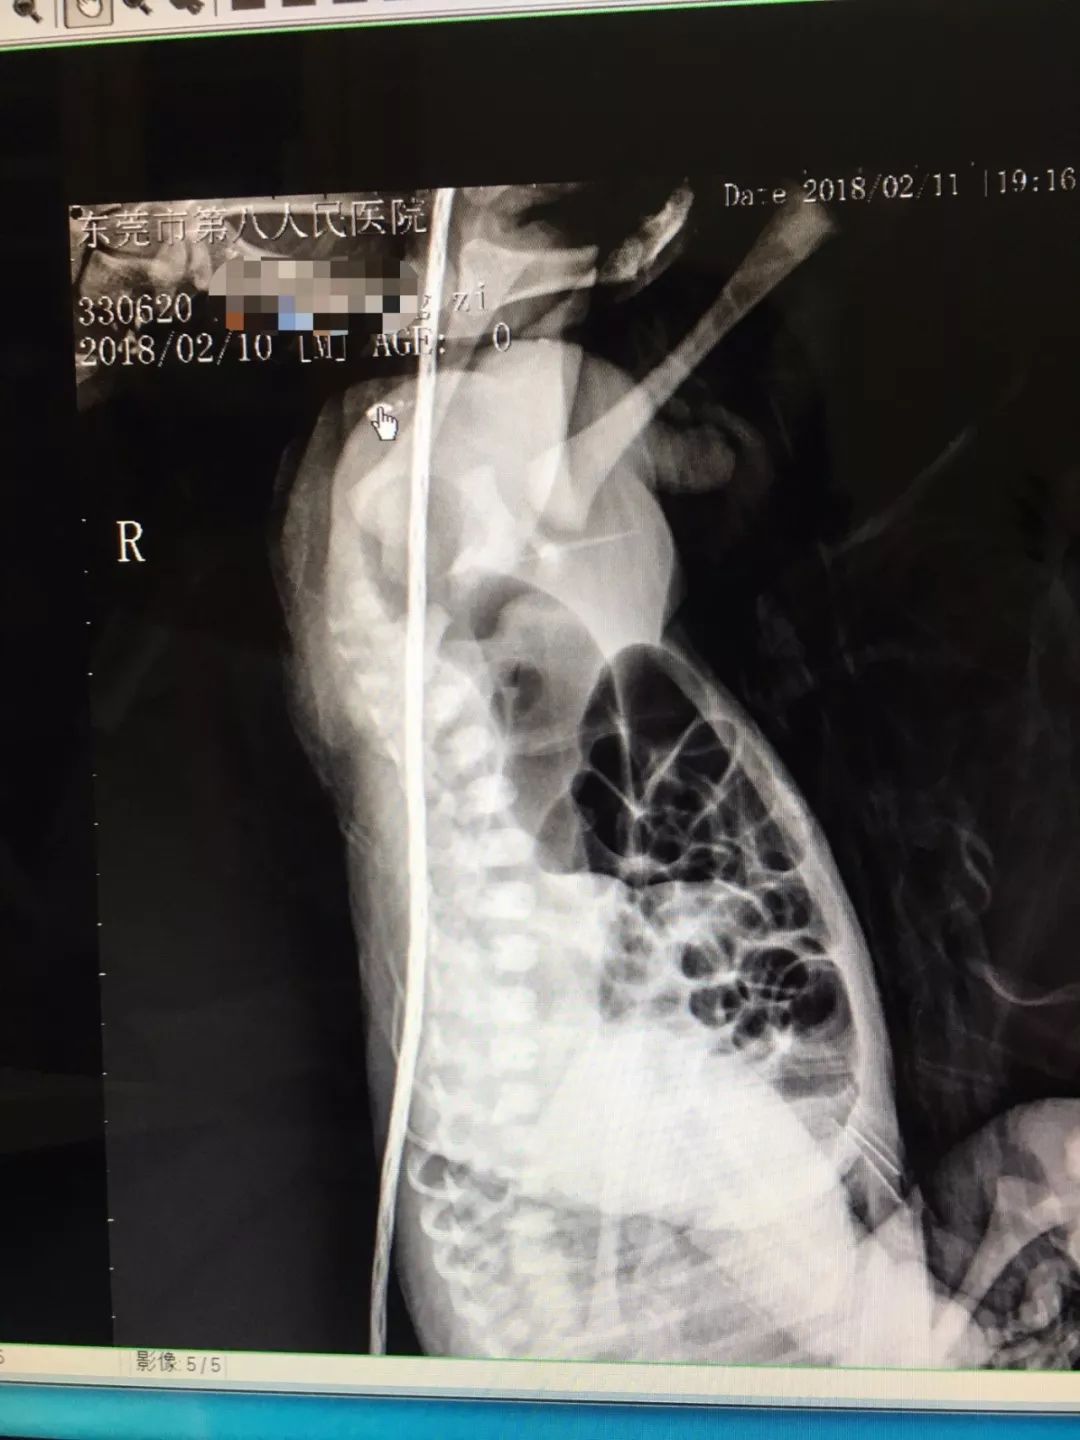

(这名男婴的拍片:箭头的位置该有肛门)

马主任介绍,该男婴本该有肛门的位置,仅有一处皮肤褶皱,像个假口袋,在医学上叫“肛门闭锁”。